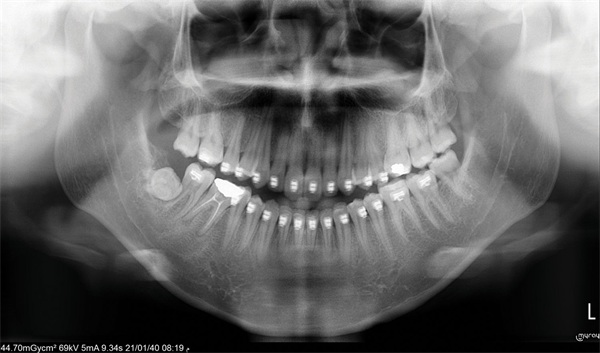

The cephalometric findings pointed clearly toward vertical maxillary excess. The asymmetric molar relationships, increased lower facial height, and posterior crossbite tendency all reinforced a picture that self-ligating brackets and wire changes were never going to resolve. The community’s response was equally clear: The ideal treatment is orthognathic surgery. The harder question was what to do when surgery is not a viable option (Figs. 1–10).

Fig. 2

Before any treatment planning conversation could move forward, one Townie raised a foundational concern: The incoming records may not yet be sufficient. Working with mounted casts was suggested as a prerequisite given the complexity of the case. The asymmetric molar relationships and transverse discrepancy made it difficult to fully assess arch coordination from photographs and radiographs alone.